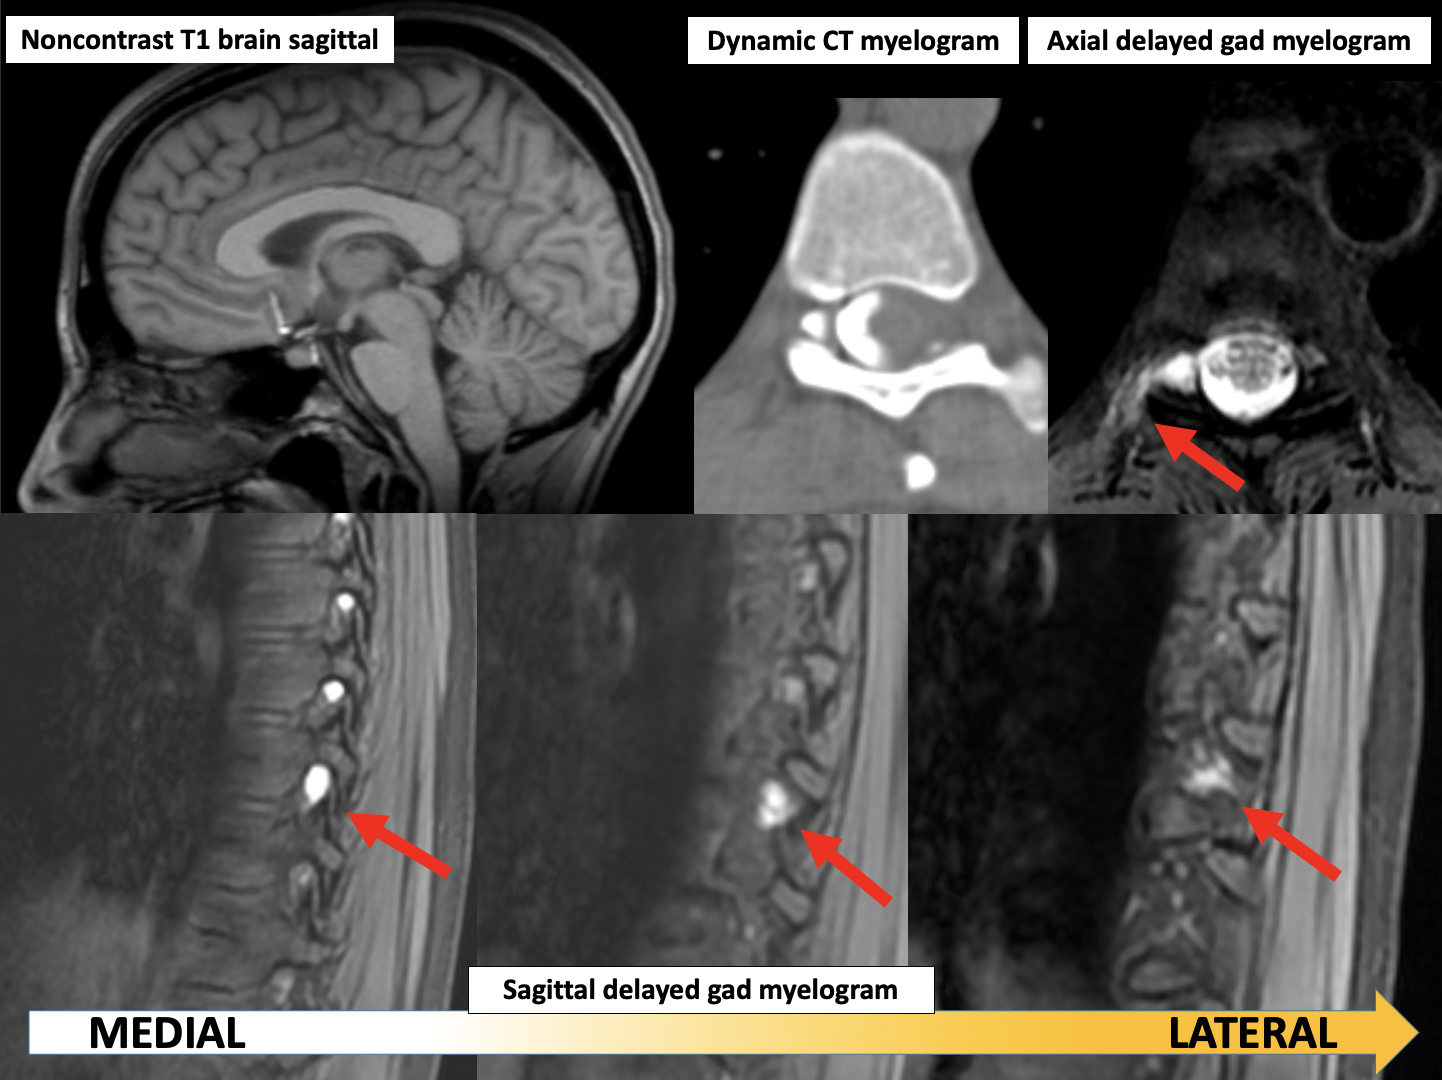

CT Myelography: Clinical Indications and Imaging Findings | RadioGraphics